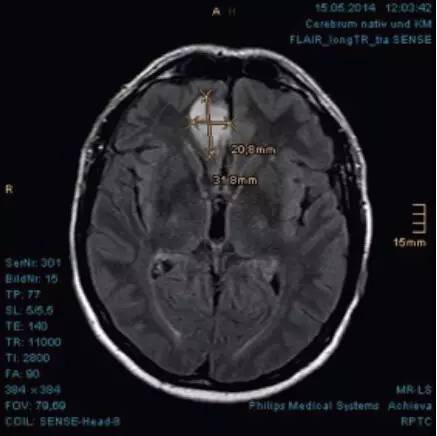

6.治疗过程影像检测:

2014年5月15日质子治疗前肿瘤大小约为20.8x31.8mm